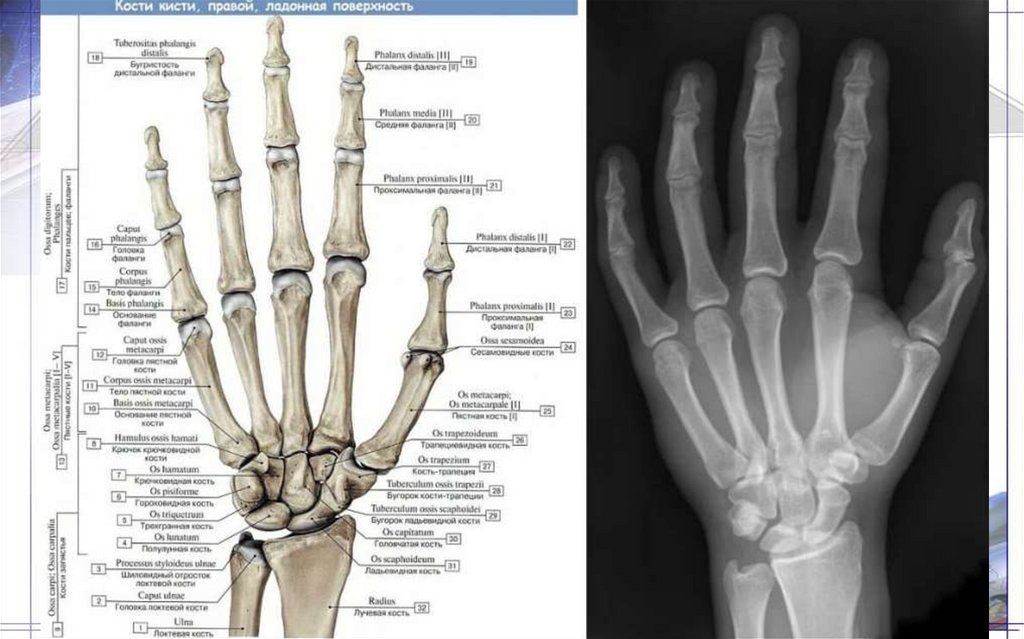

47. Как запомнить кости запястья!

• На Ладье (ладьевидная кость) при Луне

(полулунная кость) Трое (трехгранная кость)

ели Горох (гороховидная кость), И снимали с

Крючка (крючковатая кость) рыбьи Головы

(головчатая кость), Да сложили потом

Трапециевидную(трапециевидная кость)

Трапецию (трапеция)